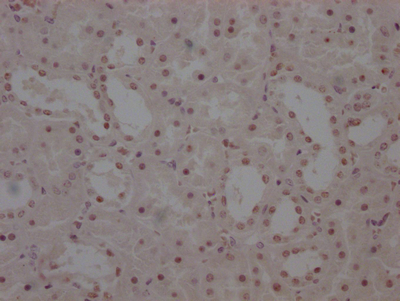

Immunohistochemistry of paraffin-embedded human lung cancer using CSB-PA010418PA10nphHU at dilution of 1:100